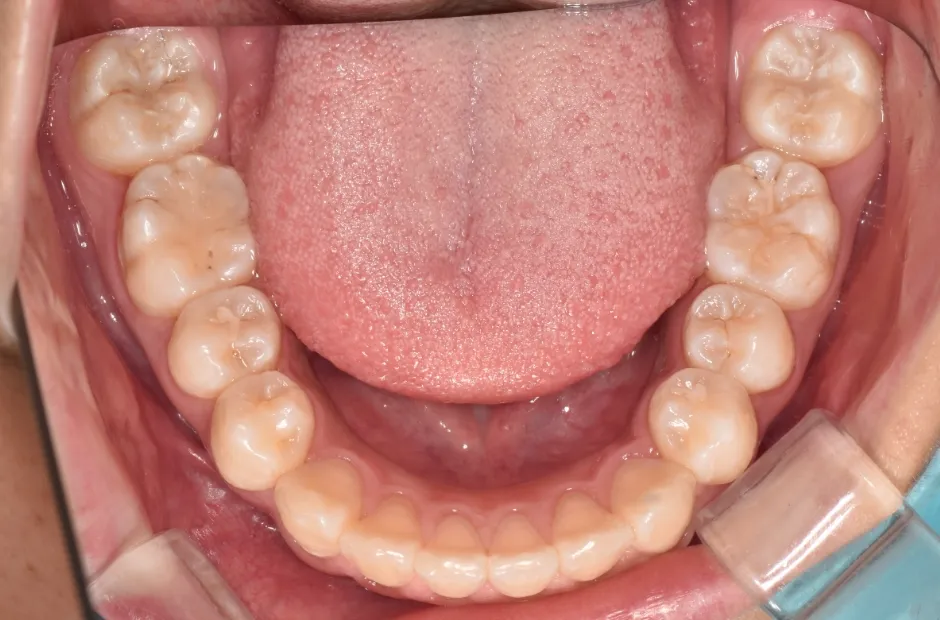

拡大床装置

叢生

| 診断名・主訴 | 叢生 |

|---|---|

| 年齢・性別 | 10歳・女性 |

| 治療期間・回数 | 2年半 |

| 治療に用いた主な装置 | 拡大床装置 |

| 抜歯部位 | なし |

| 治療費 | 30万円(税抜) |

| リスク・副作用 | 装置による違和感・疼痛・歯肉退縮・歯根吸収・虫歯のリスクなど |

治療前

治療中

治療後